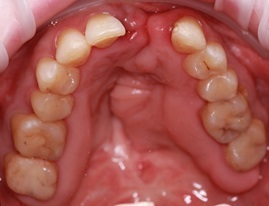

Пациентка М. обратилась с жалобами на нарушение эстетического вида фронтальной группы зубов верхней челюсти, сколы композитного материала, желанием изменить и индивидуализировать свою улыбку.

Ре-дизайн улыбки

В процессе диагностического исследования выявлено: наличие несостоятельных композитных реставраций зубов 1.4, 1.3, 1.2, 1.1, 2.1, 2.2, 2.3, 2.4 множественные сколы, дебондинг, рецидивирующий кариес.

Эстетическая реабилитация пациента

Оптимальное позиционирование фронтальной группы зубов

Создание гармонии в работе ВНЧС за счет выражения "клыковой направляющей"

По результату планирования ортопедической реабилитации составлен предварительный план лечения:

1. Выполнение профессиональной гигиены полости рта

2. Восстановление дефектов твердых тканей зубов 1.4, 1.3, 1.2, 1.1 ,2.1, 2.2, 2.3 ,2.4

3. Проектирование индивидуальной улыбки, согласно эстетическим требованиям пациента

4. Изготовление безметалловых конструкций зубов 1.4, 1.3, 1.2, 1.1 ,2.1, 2.2, 2.3 ,2.4

В процессе препарирования восстановлены дефекты твердых тканей зубов

Моделирование будущей эстетической улыбки пациента согласно индивидуальным пожеланиям.

Сравнение полученного результата